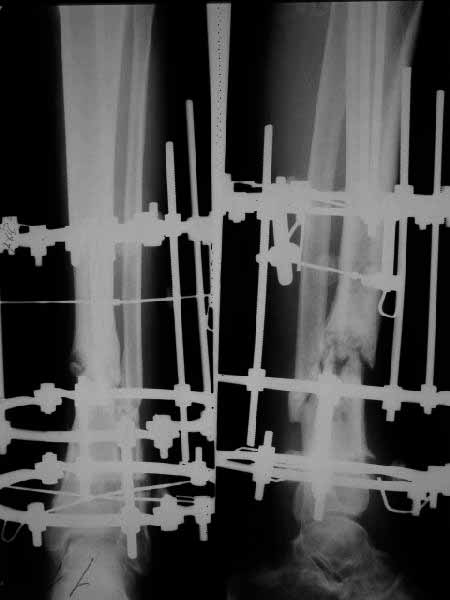

The case was presented in the Russian ortho list. A male 27 years old sustained an open (GA-II) fracture of the tibial shaft. Plating was performed on admission. Early deep infection developed, so the plate was removed and a small wire Ilizarov ex-fix applied. A sinus persisted about 6 month, after removal of a small fragment soft tissues got closed. All seemed to be healing, but on x-ray prior expected hardware removal in Dec 2004 a nonunion was seen (attached). Wire tracts now look quiet. The patient walks with a cane. He is tired with 1.5 year of ex-fix and requests to do something.